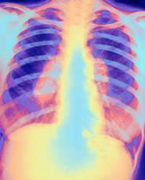

Странам ЕС угрожает новая опасность – устойчивый к лекарственным препаратам туберкулез. С таким заявлением выступили представители ВОЗ.

Согласно статистике ВОЗ, проблема лекарственной устойчивости микобактерий туберкулеза наиболее остро стоит в странах бывшего СССР (включая, к сожалению, Россию), а также в странах Восточной Европы, где доля случаев устойчивого туберкулеза достигает 14 процентов. На втором месте стоят Южная Африка, Израиль и некоторые районы Китая. Причем для современного резистентного туберкулеза характерно явление, называемое «суперрезистентностью» - то есть устойчивость не к одному классу противотуберкулезных препаратов, а к 3-4 – оно встречается в 80 процентах случаев.